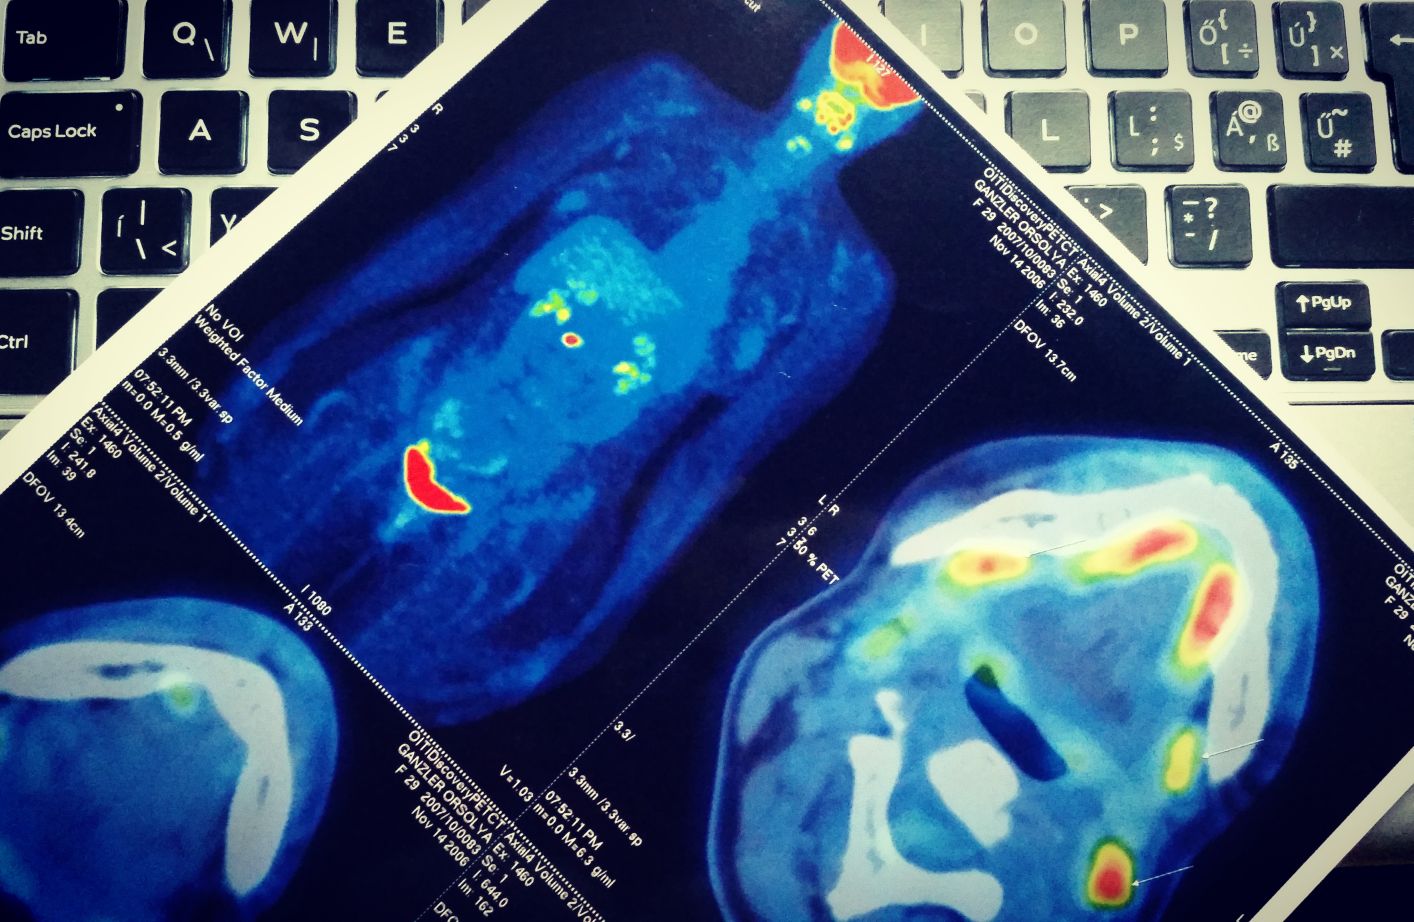

„A diagnózist mostanra egyre részletesebb immunológiai és molekuláris genetikai vizsgálatok segítenek pontosítani, amelyek a modern, célzott terápiákhoz is iránymutatást adnak. A betegség kiterjedésének feltérképezésében az esetek többségében egyeduralkodóvá vált a PET CT, de számos esetben szükség lehet kiegészítő vizsgálatokra (csontvelő vizsgálat, gyomor-bélrendszer eszközös vizsgálata). A diagnózis pontosítása mellett

ezek a vizsgálatok egyre nagyobb biztonsággal találják meg a rejtőzködő beteg sejteket is,de hasonlóan egyre nagyobb biztonsággal képesek kizárni is a limfómát. Mindezekhez persze elengedhetetlen a megfelelő patológiai centrumokban történő szövettani feldolgozás és véleményezés, ahol a technikailag egyre bonyolultabb eljárásokat megfelelő szinten tudják végezni.”